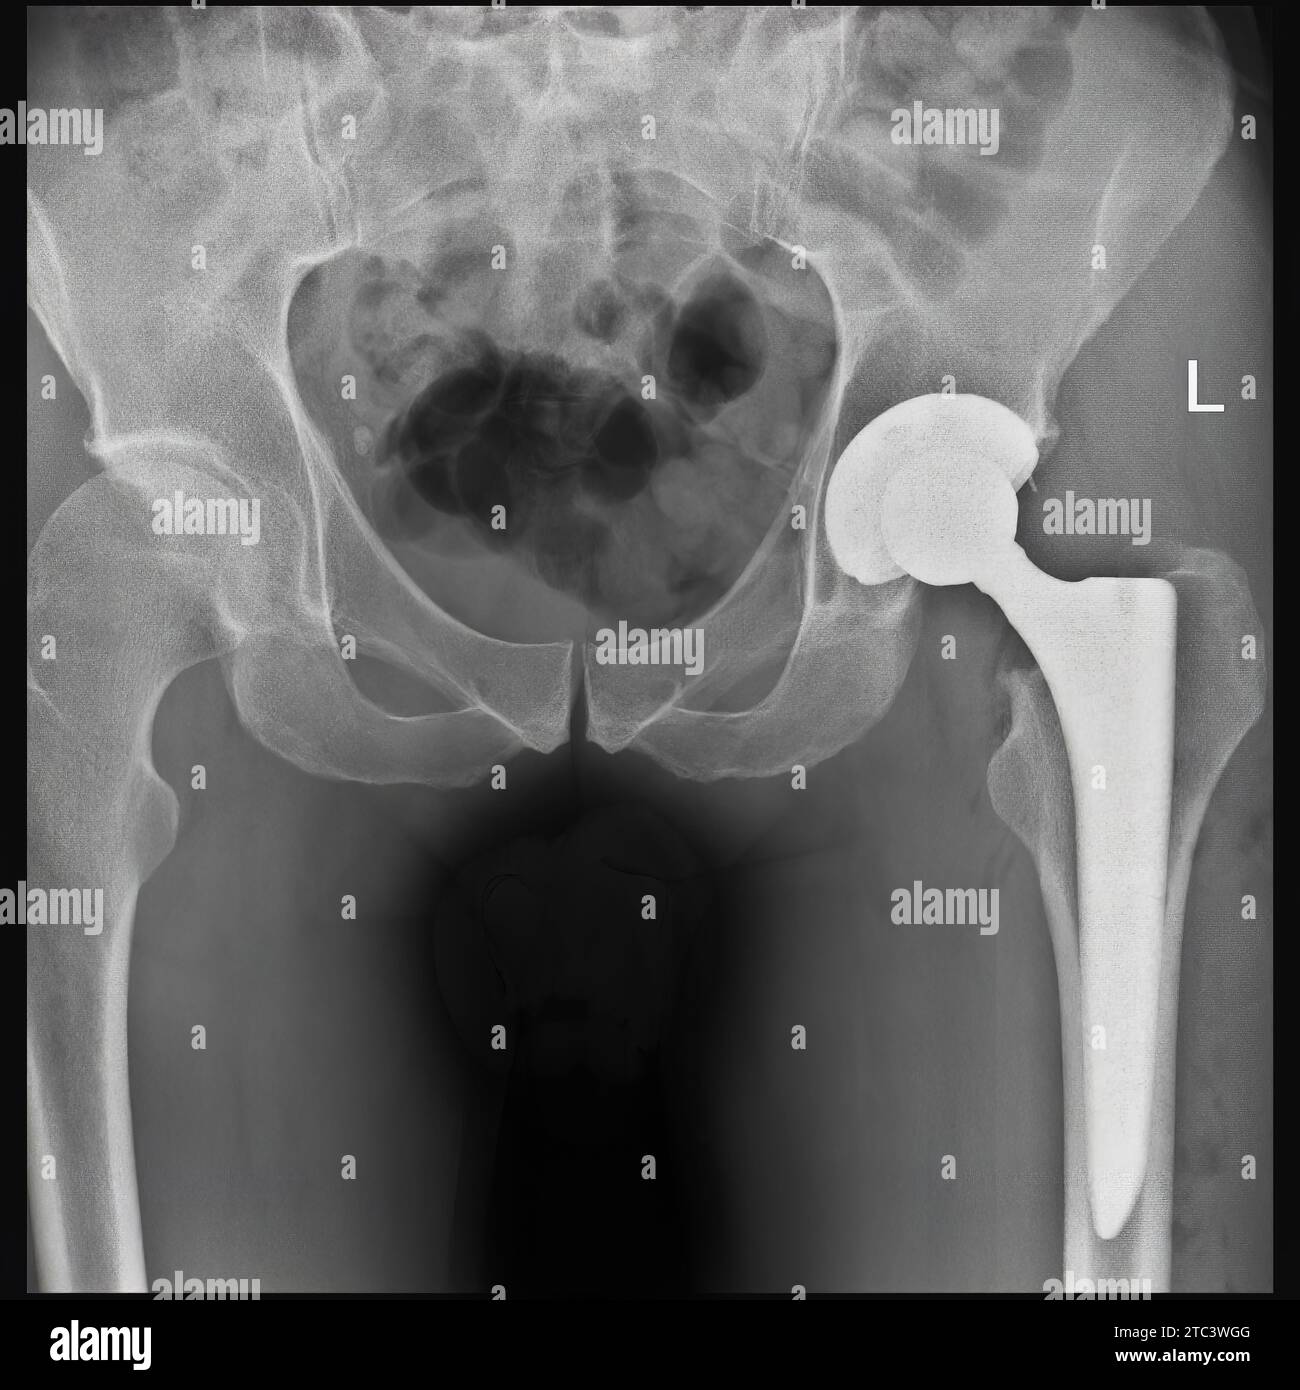

From pixels.com

Dislocated Hip Replacement, Xray Photograph by Du Cane Medical Imaging Ltd Total Hip Replacement Xr Total hip replacement is one of the most widely performed surgeries. There are three main categories of replacement: Arthroplasty of the hip may be categorized as a total hip arthroplasty or a hemiarthroplasty. This article reviews the current status of hip replacement including different types and techniques of hip replacement, various designs of. Extended reality (xr), including virtual reality, augmented. Total Hip Replacement Xr.